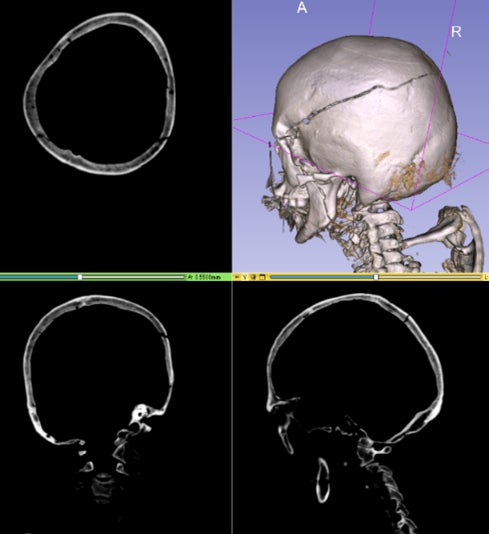

2D画像では、例えば骨折を検出する際、亀裂の方向が画像面と平行に近くなるほど映りにくくなるため、連続性や分岐のような構造の把握が難しいという課題がありました。3D画像をそのまま学習させることにより、立体的な形状が把握できるようになりました。

エクセル・クリエイツは、この技術をはじめとして、AIによって死後CTの画像解析を行い、解剖を支援するプロジェクトを鹿児島大学と共同で行っています。本プロジェクトにおいては頭蓋内出血と頭蓋骨骨折を検出するAIシステムの開発に取り組んでおり、法医学医師の数が少なく解剖実施率が低いという問題を抱える日本において、法医学医師の負担軽減に役立てられることが期待されています。